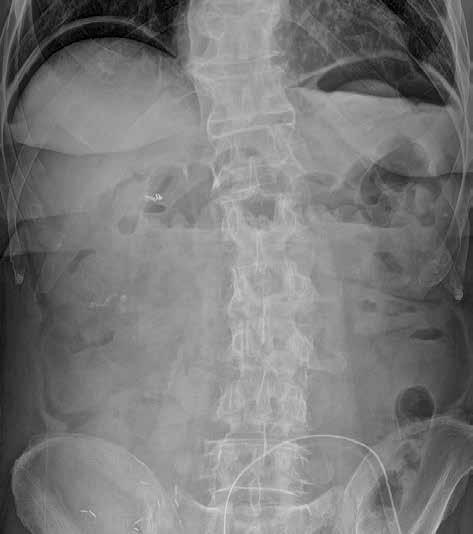

Prostý snímek břicha je stále jednou z nejlevnějších a nejdostupnějších zobrazovacích metod, využívaných při vyšetření nemocných s náhlou příhodou břišní. I když jeho význam klesá a dnes toto vyšetření nelze považovat za „metodu první volby“, má přesto i v době výpočetní tomografie (CT), ultrazvuku (UZ) a MR (magnetické rezonance) využití při podezření na střevní obstrukci či perforaci trávicí trubice, při hodnocení polohy drénů nebo detekci rentgenkontrastního tělesa (obr. 1).

Snímek břicha horizontálním paprskem vestoje se provádí s cílem zobrazit hladinky a volný vzduch v dutině břišní. Jako hladinky označujeme tzv. hydroérický fenomén neboli rozhraní mezi tekutinou a plynem v lumen střeva (obr. 3). Fyziologicky obsahuje tenké střevo cca 200 ml vzduchu a 2000 ml tekutiny, která však stále cirkuluje. Hladinky, které se na hranici tekutina/plyn ve střevních kličkách tvoří, můžeme zachytit i u zdravého jedince, u pacientů s malasimilačním syndromem a u nemocných s paralytickým ileem. Nejčastěji se s hladinkami setkáváme u nemocných s mechanickou překážkou střevní průchodnosti. Někdy lze podle lokalizace a tvaru hladinek odhadnout místo a příčinu poruchy střevní pasáže. Při akumulaci tekutiny a vzduchu v lumen střeva dochází k jeho dilataci na 3,5–4 cm (někdy až 5 cm i více). K distenzi trávicí trubice dochází orálně od místa obstrukce.

Obr. 2, 3: RTG snímek břicha vleže a vestoje. Ileus tenkého střeva. Vleže je dobře patrná dilatace kliček tenkého střeva nad 3 cm (2). Tenké střevo odlišíme od tlustého přítomností plicae circulares, které obkružují celý obvod lumen střeva. Vstoje vidíme v tenkém střevě hladinky (3).